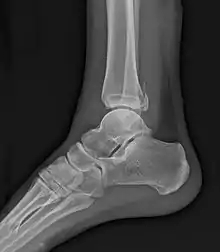

La fracture de Maisonneuve comprend une rupture du ligament deltoïde ou une fracture-avulsion horizontale de la malléole interne, associée à une longue fracture oblique de la fibula (péroné).

La fracture est associée à une déchirure de la partie distale de la syndesmose tibio-fibulaire et de la membrane interosseuse avec parfois une lésion du nerf fibulaire (nerf péronier commun ou nerf sciatique poplité externe) qui passe au niveau du col de la fibula. Cette atteinte du nerf peut entraîner une paralysie de la loge musculaire antérieure de la jambe, d’où l'impossibilité de relever le pied.